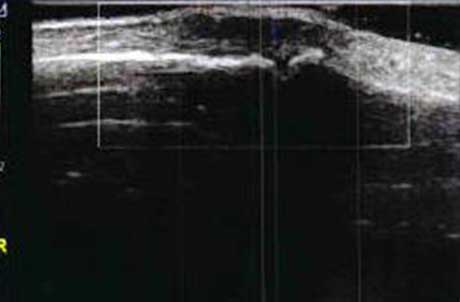

3、准确判断关节积液增加,精准判定RA严重程度

类风湿关节滑膜炎症会导致滑液渗出不断增多,形成关节腔积液。肌骨超声少可发现1ml的积液,能对关节腔积液量及位置准确定位,通过检测判定关节腔内液性边界清楚的无回声区、细点状回声或细微的低回声条纹,判断其宽度和深度衡量积液量的多少,进而评估RA的严重程度。

Ⅰ级微量积液

滑膜囊内见前后径3.55mm液性暗区,呈椭圆形

Ⅱ级较多量积液

暗区内有团状高回声,可见深度达6.46mm液性暗区

Ⅲ级大量积液

关节囊扩张,可见大范围液性暗区,髌上囊积液深度达11.2mm